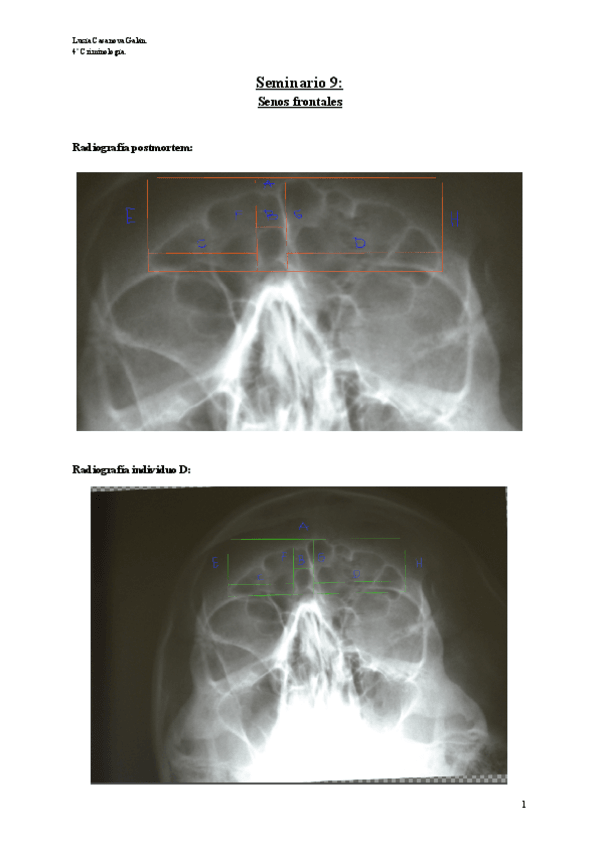

He publicado nuevos practicas de 4º Técnicas de Identificación Forense: Seminario-9-Senos.pdf

TEMA-10-Estudio-radiografico-de-senos-paranasales-2.pdf